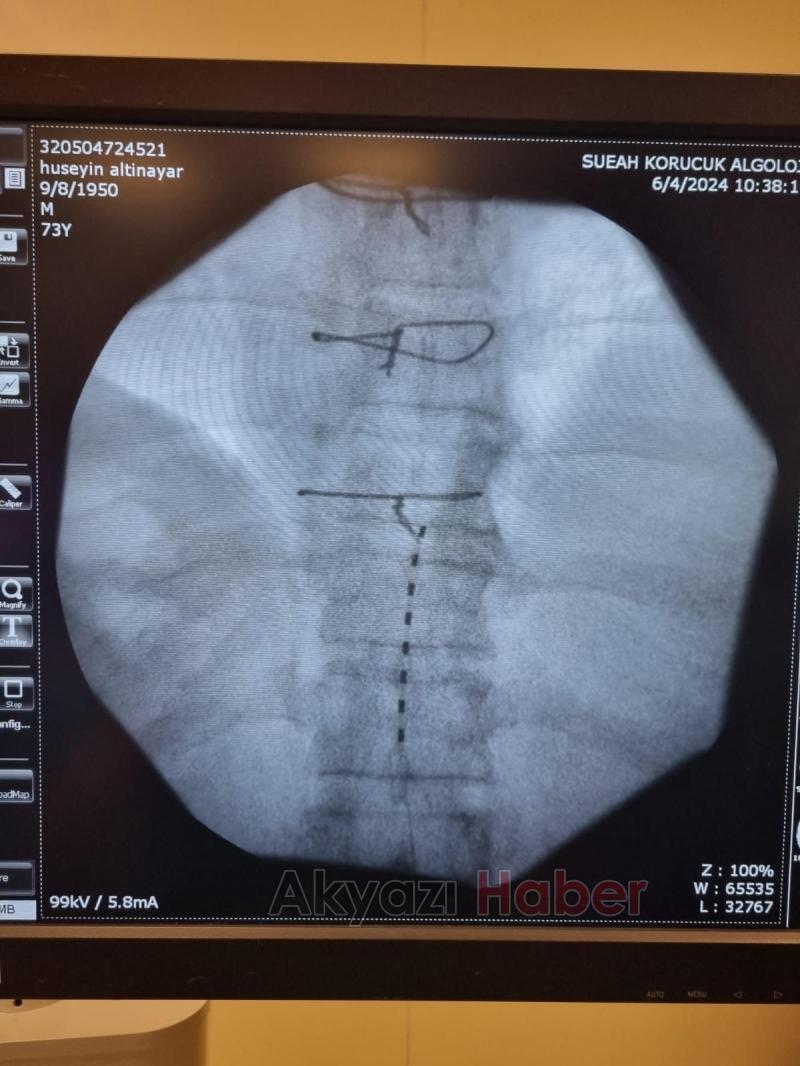

Yıllardır ayağındaki ağrıya çare bulamayan hasta Sakarya Eğitim ve Araştırma Hastanesi (SEAH) Algoloji Kliniğine başvurdu. 7 yıldır ayağında yanma ve ağrı şikayeti (Kronik nöropatik hastalığı) olduğunu belirten hastanın şikayetlerinin son bulması için klinik hekimleri tarafından özellikli bir işlem olan Ağrı Pili (Spinal Kord Stimülatörü) uygulanmasına karar verildi.

Algoloji Kliniğinde Prof. Dr. Kemal Nas, Doç. Dr. Savaş Şencan, Uzm. Dr. Rıdvan Işık ve Asistan Dr. Sena Ünver tarafından işleme alınan hastanın operasyonu başarıyla tamamlandı. İşlem sonrası servise alınan hastanın uzun yıllardır hayatını olumsuz etkileyen müzmin ayak ağrısın geçtiği belirtilirken, ağrı uzmanı hekimler tarafından uygulanan yöntemin son derece etkili bir tedavi olduğu kaydedildi.